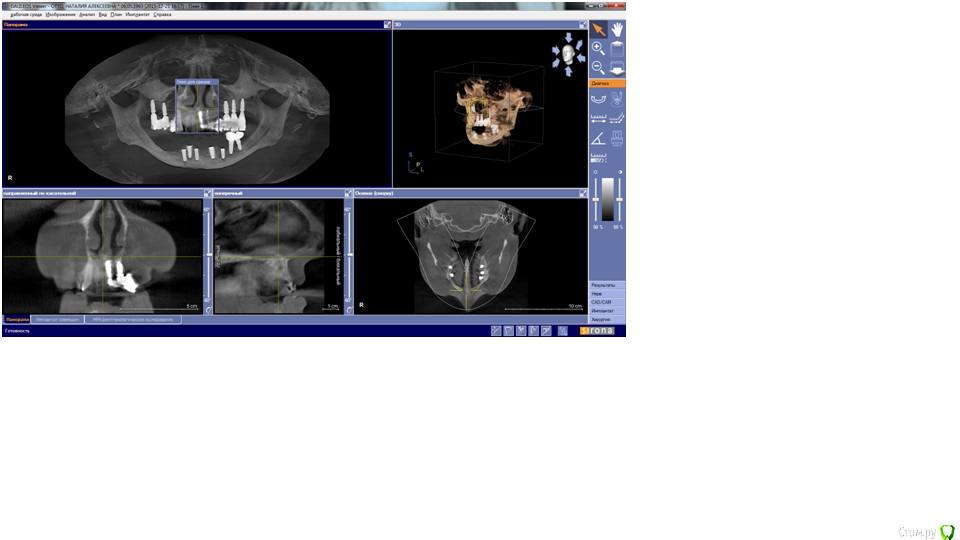

Nataly07 Опубликовано 7 января, 2016 Поделиться Опубликовано 7 января, 2016 Уважаемые доктора, была бы очень благодарна вам, если бы нашли время ответить на очень важный для меня вопрос. В начале декабря 2015 была проведена операция по имплантации на нижней челюсти. Были установлены 5 имплантатов. После операции выяснилось, что с левой стороны присутствует онемение подбородка. Была сделана КТ. Хирург посмотрел снимок и сказал, что всё нормально, имплантат не касается нерва. В заключении врача-рентгенолога написано: имплантат 3.5 – апикальная треть перфорирует нижнечелюстной канал на всем протяжении в области ментального отверстия. Ниже имплантата с оральной стороны визуализируется дефект оральной компактной пластинки. В переводе с медицинского на общечеловеческий язык, что это означает и каковы должны быть дальнейшие действия?Имплантат 4.3 – ниже имплантата визуализируется сквозной дефект нижней компактной пластинки. Имплантат надо удалять? Какие могут быть последствия, если его не удалять?Снимки сделаны в программе Галилео, не знаю, как их сохранить. Ссылка на комментарий

IvanK Опубликовано 8 января, 2016 Поделиться Опубликовано 8 января, 2016 35 я бы убрал, ... Какой вариант протезирования планируется? Ссылка на комментарий

Nataly07 Опубликовано 8 января, 2016 Автор Поделиться Опубликовано 8 января, 2016 то есть 3.5 можно и не убирать? рентгенолог написал в заключении, что он перфорирует нижнечелюстной канал в области ментального отверстия, а ниже имплантата с оральной стороны визуализируется дефект оральной компактной пластинки - что это такое? С этим можно жить?) а между имплантатами 4.3 и 4.2 расстояние 1,5 миллиметра, как вы считаете, смогут они прижиться? не нарушится ли питание кости и не придется ли их потом убрать оба? ниже имплантата 4.3 - сквозной дефект нижней компактной пластинки. Такой имплантат можно сохранять? 4.1 - оголение в вестибулярной стенке коронковой трети имплантата до 4,8 миллиметров, сможет ли он в дальнейшем послужить опорой для коронки? Планируется протезирование на винтах. Ссылка на комментарий